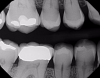

Figure 4 through Figure 11 compare various imaging modalities in three different cases, illustrating the potential of these devices to improve diagnostic capabilities.

Fig 4. Case 1. Bitewing radiograph shows no indication of caries on tooth No. 14.

Figure 4

Fig 7. Case 2. Bitewing radiograph shows no indication of interproximal or recurrent caries around the composite restoration on tooth No. 13.

Figure 7

Fig 9. Case 2. Initial opening of tooth shows caries into the dentin.

Figure 9

Fig 10. Case 3. X-ray image obstructed by amalgam restoration.

Figure 10

Fig 11. Case 3. NIR transillumination image shows recurrent caries on tooth No. 3.

Figure 11